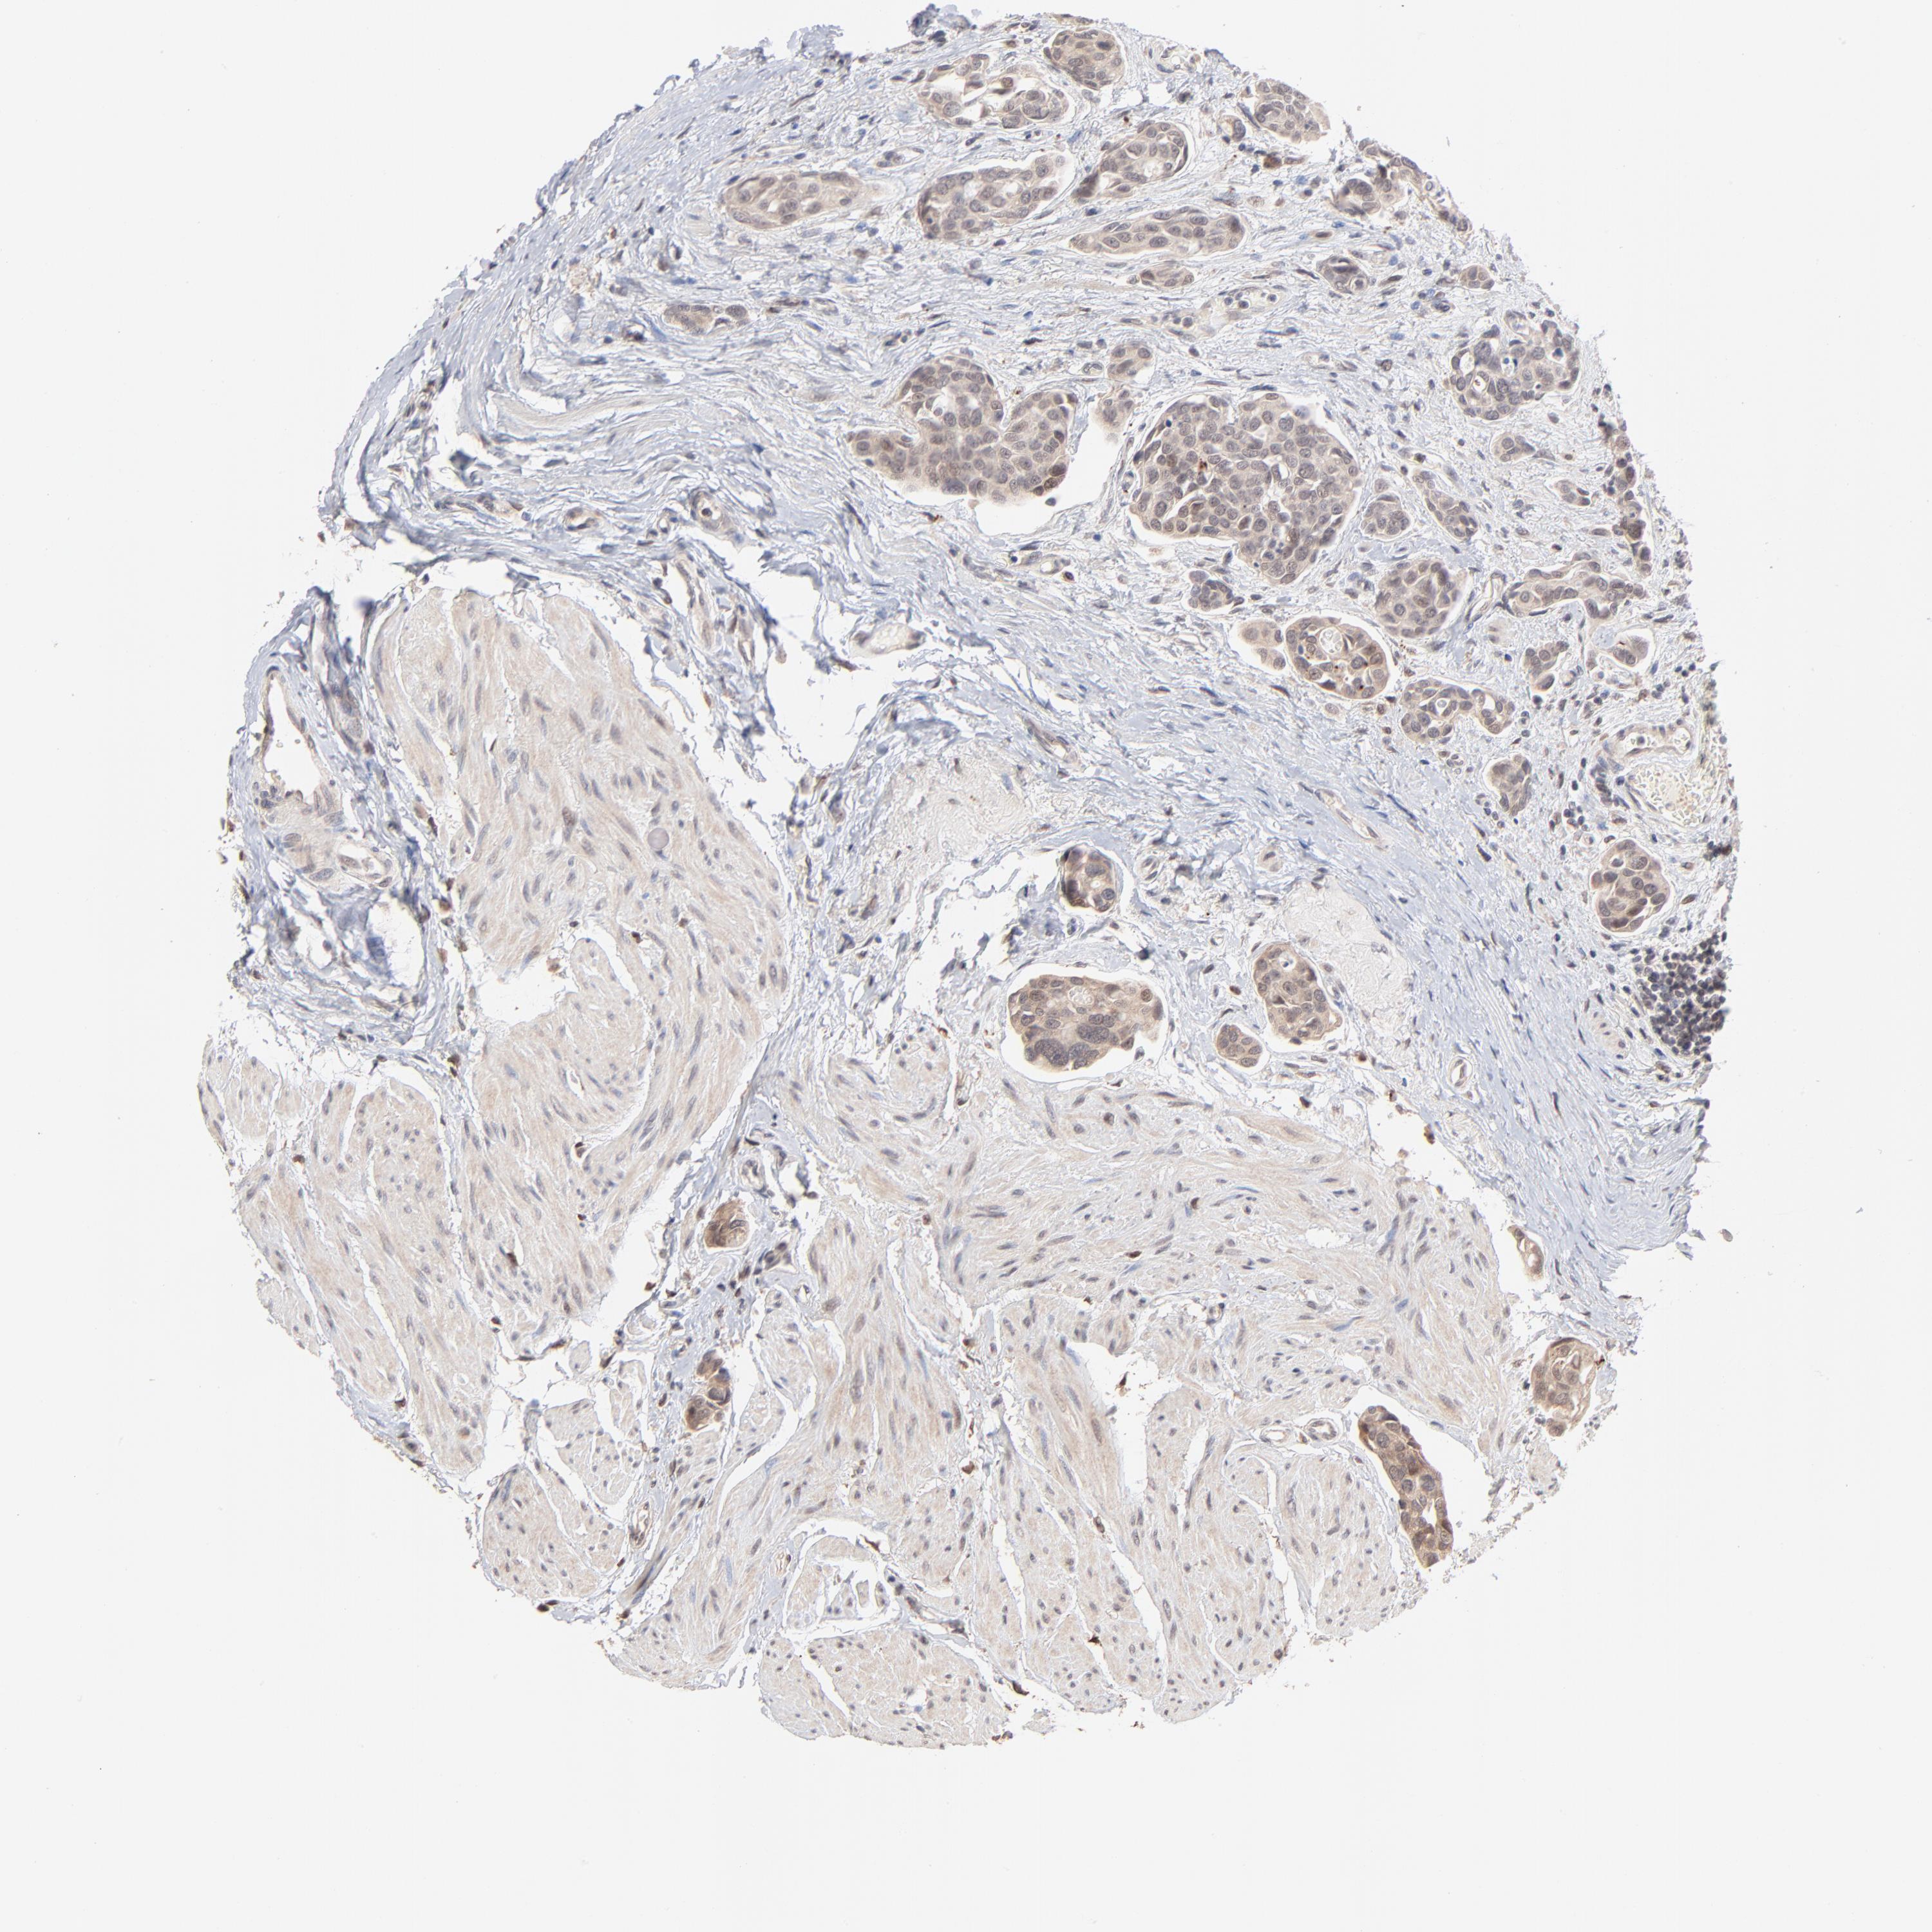

UROTHELIAL CANCER - Protein expressioni

A mouse-over function shows sample information and annotation data. Click on an image to view it in a full screen mode. Samples can be filtered based on level of antibody staining by selecting one or several of the following categories: high, medium, low and not detected. The assay and annotation is described here.

Note that samples used for immunohistochemistry by the Human Protein Atlas do not correspond to samples in the TCGA dataset.

Antibody stainingi

Antibody staining in the annotated cell types in the current human tissue is reported as not detected, low, medium, or high, based on conventional immunohistochemistry profiling in selected tissues. This score is based on the combination of the staining intensity and fraction of stained cells.

Each image is clickable and will lead to virtual microscopy that enables deeper exploration of all samples and also displays staining intensity scores, fraction scores and subcellular localization as well as patient and tissue information for each sample.

Antibody HPA003413

Staining

High

Medium

Low

Not detected

Intensity

Strong

Moderate

Weak

Negative

Quantity

>75%

75%-25%

<25%

None

Location

Nuclear

Cytoplasmic/membranous

Cytoplasmic/membranous,nuclear

Urothelial carcinoma, High grade

Urothelial carcinoma, Low grade